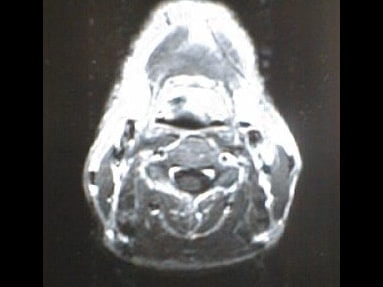

MRI画像比較

入院当時MRI画像①

入院3か月後癌消滅MRI画像①